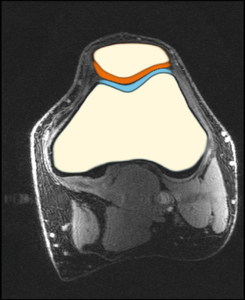

- analysis of cartilage thickness for ostheoarthitis assessment

- High-resolution data is from the University of Freiburg (T. Lange, K. Izadpanah)

- patellofemoral joint (prospective motion correction)

- depicted image is a healthy volunteer